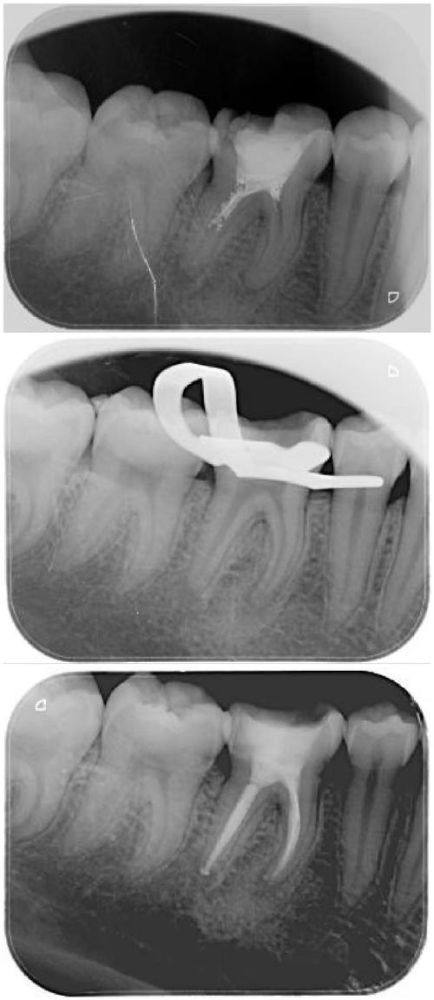

在根管治疗后,大部分患者都不会有疼痛的感觉。这是因为在治疗过程中,医生会把牙齿里的牙髓清除掉,然后用特殊的材料把牙髓腔和根管严严实实地填充起来。没了牙髓,牙齿也就少了疼痛的“导火索”,所以一般情况下不会出现疼痛反应。就好像把房子里容易着火的东西都清理出去,再把房子封得严严实实,自然就安心了。对于特别多接受根管治疗的患者来说,这是一个比较理想的状态,治疗后可以正常地饮食和生活,不用再担心牙齿疼痛带来的困扰。

根管治疗所需的时间也没有一个固定的答案。一般来说,简单的根管治疗可能一次就能完成,时间大概在一个小时左右。但如果牙齿的情况比较复杂,比如根管比较弯曲、细小,或者炎症比较重度,可能就需要多次治疗。每次治疗之间需要间隔一段时间,让牙齿有修复的时间,整个治疗过程可能会持续几周甚至几个月。所以,在治疗前,医生会根据患者牙齿的具体情况,制定个性化的治疗方案,告知患者大概的治疗时间。患者要积极配合医生的治疗,按时复诊,这样才能让治疗顺利进行。